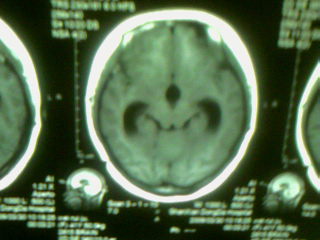

标题: MRI2125:女 45岁 头疼头晕3个月 [打印本页]

标题: MRI2125:女 45岁 头疼头晕3个月

手机照的,请各位谅解

1)考虑第四脑室脉络膜丛乳头状瘤,不排除室管膜瘤。2)阻塞性脑积水。

考虑 第四脑室室管膜瘤或脉络膜丛乳头状瘤伴梗阻性脑积水。

1)考虑第四脑室室管膜瘤,不排除脉络膜丛乳头状瘤。2)阻塞性脑积水。